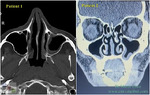

| Rhinology - Volume 63 Issue 6, Page 736-743 Serpentine Sign: evidence of airway compensation in patients with empty nose syndrome Dec 1, 2025 P-W Wu, F T-N Yu, T-J Lee, C-C Huang, P-H Chang, C-C Huang This study aimed to evaluate the presence of Serpentine Signs on computed tomography (CT) images and its impact on the clinical symptoms in patients with empty nose syndrome (ENS). METHODS: A retrospe... Journal Article |